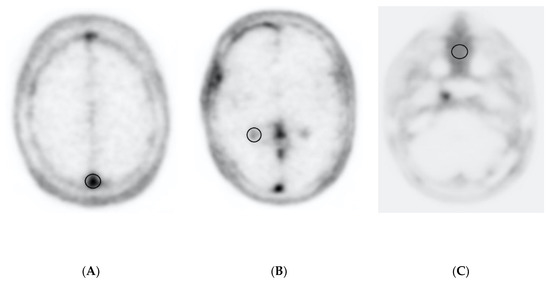

3.4. Lesion Assessment